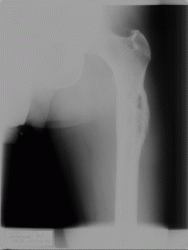

Патология костной структуры. Динамика. Ваше мнение?

Из анамнеза: 6 мес назад была травма. Не обращался,не лечился. Боли сохранялсиь,в последнее время усиливаются.

на саркому Юинга.

Биопсия это единственно правильно, на мой взгляд, больше данных за онкологию, но здесь обширный ряд: от той же саркомы Юинга (остеосаркомы, ЗФГ) до мтс, т.е имеет место некий весьма агрессивный процесс в виде остеолитической деструкции, инфильтрации кости. М.б. и поднадкостничная гематома, осложнившаяся остеомиелитом, но за полгода воспалительный процесс должен был как-то себя проявить...

Мне кажется, уже по первому снимку можно было онкологию выставлять.